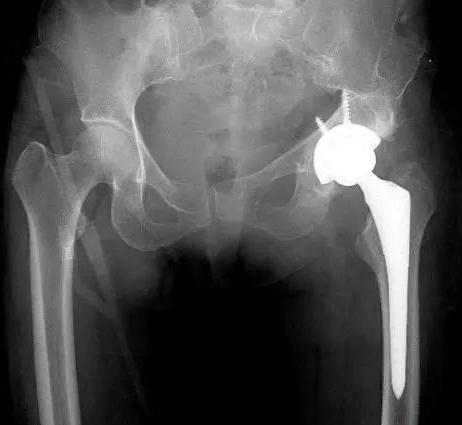

经X线和ct检查后来到医院,发现左股骨头坏死,形态异常,已经从正常位置移除,很难找到真正的髋臼、左髋臼形态,部分骨缺失。要彻底解决邹阿姨的问题,就必须进行人工替换。

手术持续时间超过2小时,出血200ml,成功地为邹阿姨左侧人工全髋关节置换,将人工髋关节准确安装在祖阿姨真正的髋臼并做了固定。邹阿姨在手术后的第4天下了床。